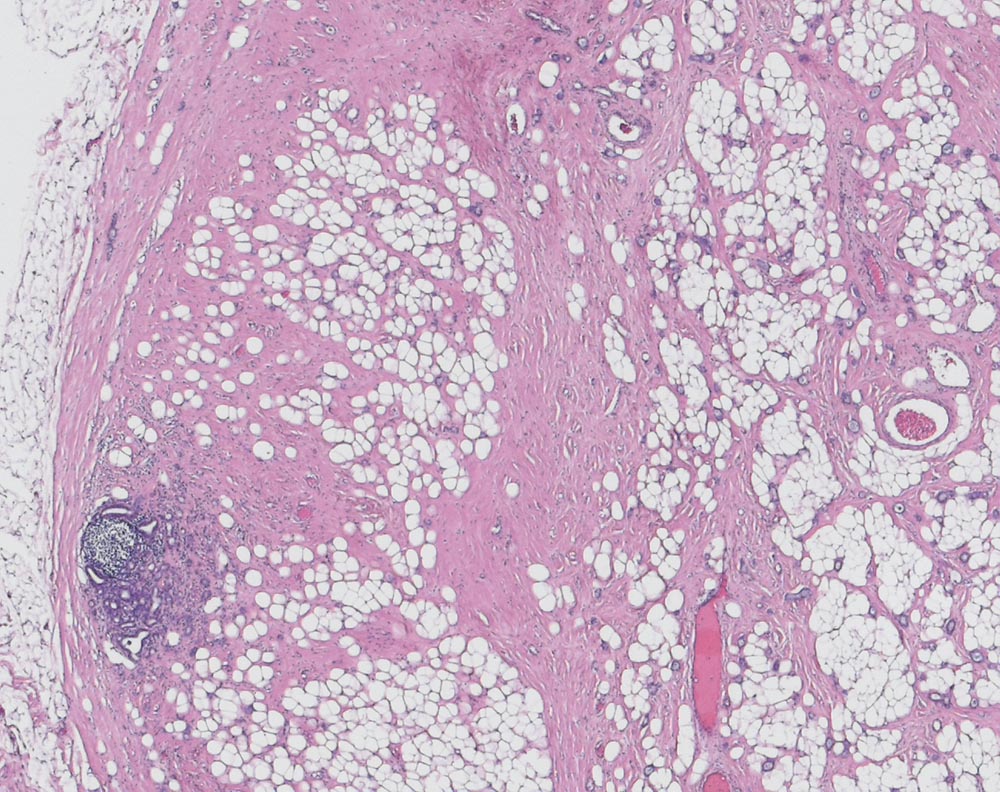

Mammakarzinom: Lymphknotenmetastase mit Regression

Vitale Metastase eines invasiv duktalen Mammakarzinoms mit fokaler Sklerose als Ausdruck einer Tumorregression nach neoadjuvanter Chemotherapie. Ausserdem reichlich Fettgewebsmetaplasie. Links im Bild ist wenig residuelles Lymphknotengewebe zu sehen.

Hochdifferenziertes invasiv duktales Mammakarzinom mit Vernarbung von ca. 30% des Tumorgewebes.

Lymphknotenmetastasen eines neoadjuvant vorbehandelten hoch differenzierten invasiv duktalen Mammakarzinoms.

Als Antwort auf die neoadjuvante Chemotherapie zeigen Lymphknotenmetastasen Hyalinisierungsfelder, Makrophagen und Schleimseen. In bis zu 30% kommt es zur vollständigen Tumorregression. In diesen Fällen sind lediglich kleine subkapsuläre Narbenfelder nachweisbar. Das Ausmass der regressiven Veränderungen ist in den Lymphknotenmetastasen meist etwas geringer als im Primärtumor, korreliert aber in der Regel mit dem Ansprechen des Primärtumors.